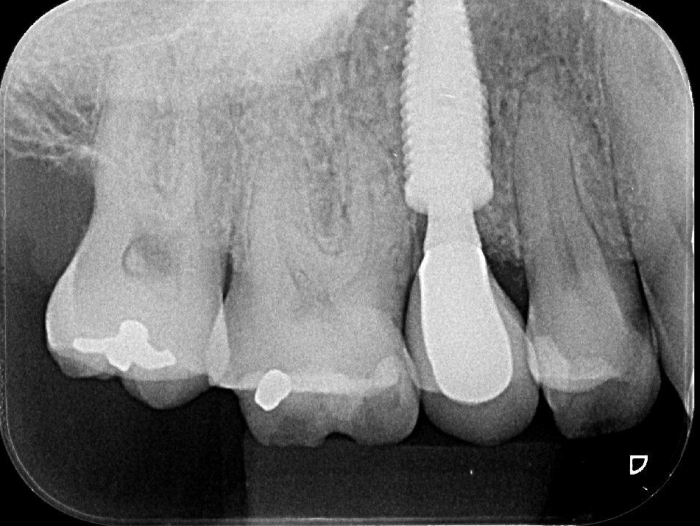

Elemento 15 fraturado

Rx Imediato